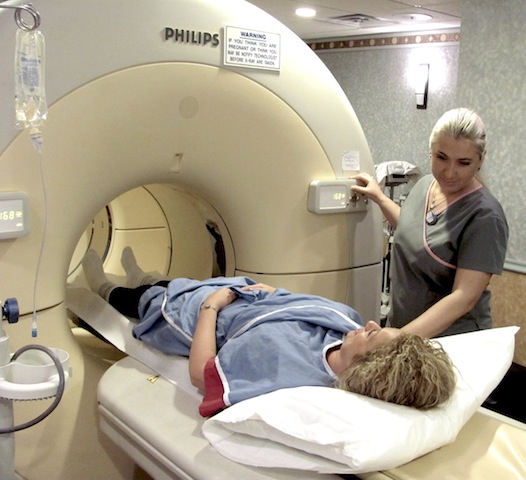

Компьютерная томография органов малого таза: оборудование и результаты исследований